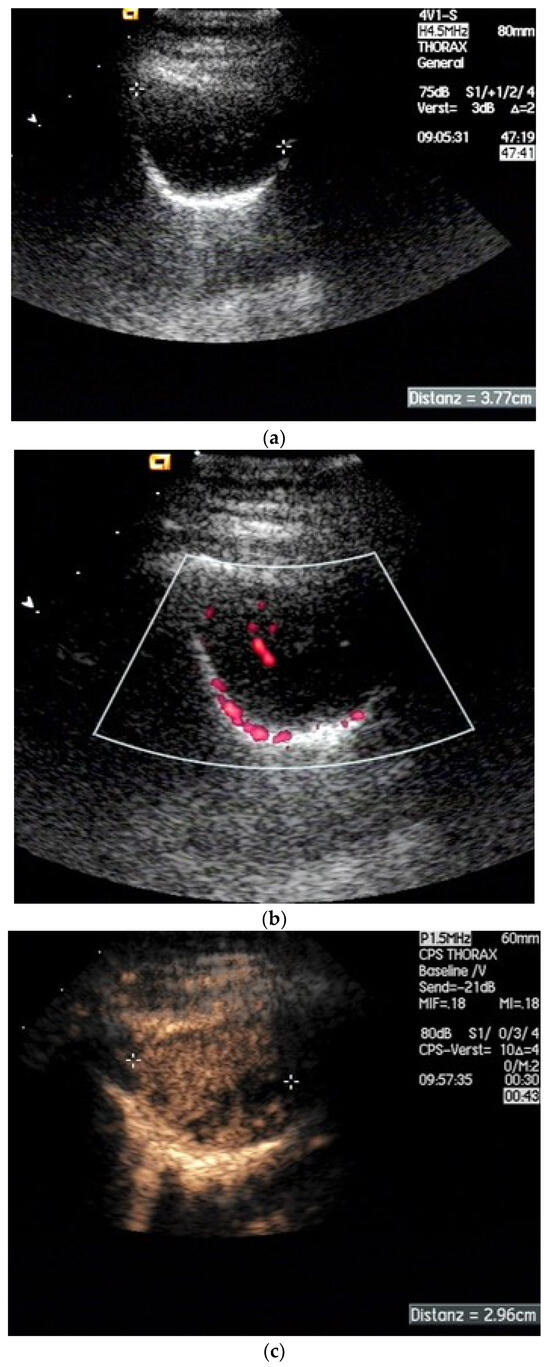

| Fibrothorax | Extensive and dense fibrosis of the visceral pleura, with fusion of the visceral and parietal pleural layers, no lung sliding. |

| Encapsulated pleural effusions | Round, smoothly circumscribed hypoechoic or anechoic masses. No evidence of macrovessels in CDI. Non-enhanced in CEUS. |